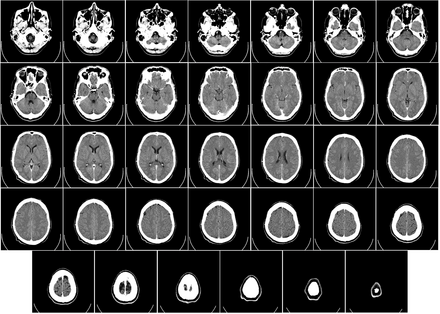

Computed Tomography (CT or CAT) Scan of the Brain

The brain can be divided into the cerebrum, brainstem, and cerebellum:

Cerebrum. The cerebrum (supratentorial or front of brain) is

composed of the right and left hemispheres. Functions of the

cerebrum include: initiation of movement, coordination of

movement, temperature, touch, vision, hearing, judgment,

reasoning, problem solving, emotions, and learning.Brainstem. The brainstem (midline or middle of brain) includes

the midbrain, the pons, and the medulla. Functions of this area

include: movement of the eyes and mouth, relaying sensory

messages (hot, pain, loud, etc.), hunger, respirations,

consciousness, cardiac function, body temperature, involuntary

muscle movements, sneezing, coughing, vomiting, and swallowing.Cerebellum. The cerebellum (infratentorial or back of brain) is

located at the back of the head. Its function is to coordinate

What are the reasons for a CT scan of the brain?

A CT of the brain may be performed to assess the brain for tumors and

other lesions, injuries, intracranial bleeding, structural anomalies

(e.g.,

hydrocephalus

, infections, brain function or other conditions), particularly when

another type of examination (e.g., X-rays or a physical exam) are

inconclusive.

A brain CT may also be used to evaluate the effects of treatment on

brain tumors

and to detect clots in the brain that may be responsible for

strokes

. Another use of brain CT is to provide guidance for brain surgery or

biopsies of brain tissue.